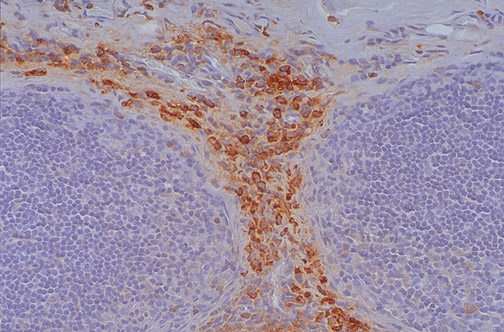

This normal lymph node has mainly interfolliclular cells that are positive for myeloperoxidase.